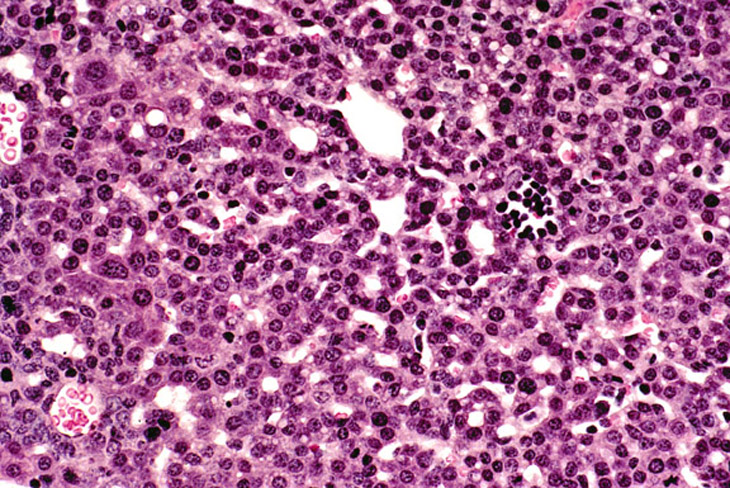

Liver from a 2-week old wild type FVB mouse.